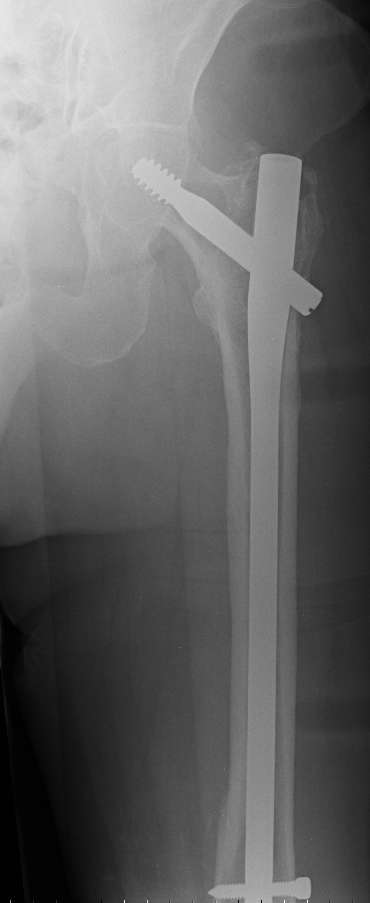

- It is an long, spiral, metaphyseal fracture – very good chance of healing (will not be any need for any bone cement…bone substitute – filler)

- I would use: distal femoral locking plate with few cerclage wires in midsegment and some unicortical locked screws and cerclage wires proximal…

I would consider retrograde femoral interlocking nail after Gamma nail removal during the same surgery.

In my opinion the femoral bone looks osteoporotic, but no bone defect is visible to justify bone cement.

If we have a ready entry point after the gamma removal why perforate the intact knee for another entry - why not just insert a longer antegrade

nail? We definitely would do this. Of course retrograde nailing as well as locked plating would do the job but antegrade nailing in this case is

least invasive among mentioned options.

1. Removal of the nail in elderly, frail lady is not a small procedure (timing and blood loss)

2. It is hard to do "good fixation" of distal fracture through antegrade approach.... and probably distal incision (more than just

for distal locking) would have to be made anyway (reduction, cerclage wires...).

3. Retrograde nail (small diameter in large bone) does not allow for good, stable fixation (often malalignment) and early weight bearing (I have seen the locking screws and nail cutting through the distal femur into the knee joint - in osteoporotic bone, heavy persons)

4. We could treat this fracture like there is no a nail - new locking plates allow for secure fixation.... two similar cases are attached...